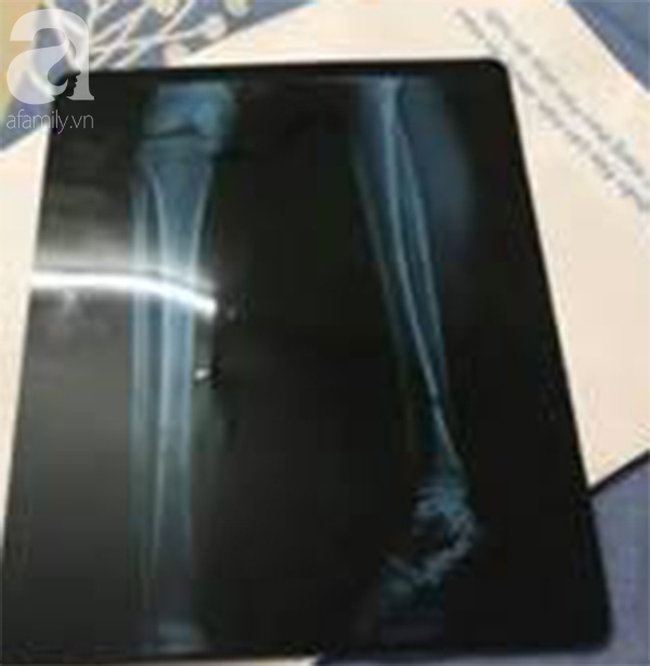

Tuy nhiên sau đó tài xế không liên lạc được, khiến nạn nhân phải chia sẻ lên mạng xã hội (Ảnh chụp Xquang)